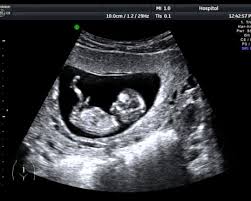

ತೆಲಂಗಾಣದ ವಾರಂಗಲ್ ಜಿಲ್ಲೆಯ ನರಸಂಪೇಟೆ ಪಟ್ಟಣದ ಸ್ಕ್ಯಾನಿಂಗ್ ಕೇಂದ್ರವೊಂದರಲ್ಲಿ ದೋಷವೊಂದು ಕಂಡುಬಂದಿದ್ದು, ಅಪ್ರಾಪ್ತ ಬಾಲಕಿಯೊಬ್ಬಳು ಗರ್ಭಿಣಿ ಎಂದು ತಪ್ಪಾಗಿ ವರದಿಯಾಗಿರುವ ಘಟನೆ ನಡೆದಿದೆ. ಅನಂತರ ಉದ್ವಿಗ್ನತೆ ಉಂಟಾಗಿದೆ. ಇದು ಆಕೆಯ ಕುಟುಂಬದಿಂದ ಆಕ್ರೋಶಕ್ಕೆ ಕಾರಣವಾಯಿತು ಮತ್ತು ಪೊಲೀಸ್ ತನಿಖೆ ನಡೆಸಲಾಯಿತು.

ಹೊಟ್ಟೆ ನೋವಿನ ಬಗ್ಗೆ ದೂರು ನೀಡಿದ ನಂತರ ಬಾಲಕಿ ಆರಂಭದಲ್ಲಿ ಸ್ಥಳೀಯ ಸ್ಕ್ಯಾನಿಂಗ್ ಸೌಲಭ್ಯಕ್ಕೆ ಭೇಟಿ ನೀಡಿದ್ದಳು. ಕುಟುಂಬದ ಪ್ರಕಾರ, ಸ್ಕ್ಯಾನ್ ವರದಿಯಲ್ಲಿ ಆಕೆ ಗರ್ಭಿಣಿ ಎಂದು ಘೋಷಿಸಲಾಗಿದ್ದು, ಇದು ಆಕೆಯ ಕುಟುಂಬದವನ್ನು ಆಘಾತಕ್ಕೊಳಪಡಿಸಿತು.

ಮಾಹಿತಿಯ ಪ್ರಕಾರ, ವಾರಂಗಲ್ನಲ್ಲಿ ವೈದ್ಯರು ನಂತರ ಬೇರೆ ಸ್ಕ್ಯಾನಿಂಗ್ಗೆ ಸಲಹೆ ನೀಡಿದ್ದು, ಅಲ್ಲಿ ಖಾಸಗಿ ನರ್ಸಿಂಗ್ ಹೋಂ ವಿವರವಾದ ಪರೀಕ್ಷೆಗಳನ್ನು ನಡೆಸಿದೆ. ಪರೀಕ್ಷೆಯಲ್ಲಿ ಹುಡುಗಿ ಗರ್ಭಿಣಿಯಾಗಿಲ್ಲ ಆದರೆ ಗರ್ಭಾಶಯದಲ್ಲಿ ಸಣ್ಣ ಅಂಗಾಂಶದ ಬೆಳವಣಿಗೆ ಕಂಡುಬಂದಿದೆ. ನಂತರ ವೈದ್ಯರು ಬೆಳವಣಿಗೆಯನ್ನು ತೆಗೆದುಹಾಕಲು ಸಣ್ಣ ಶಸ್ತ್ರಚಿಕಿತ್ಸೆ ನಡೆಸಿದರು.